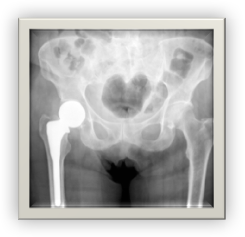

• The following Stryker hip implants have been recalled:

• LFIT V 40Recalled in 2016: In August 2016, Stryker sent out an urgent medical device recall notification on its LFIT V40 Femoral Head implant. Potential hazards of the LFIT V40 implant include disassociation of femoral head from hip stem and the release of excessive metallic debris into the body. This has been particularly problematic when the LFIT V40 femoral head is combined with an Accolade or Citation stem. Stryker uses LFIT V40 femoral heads in the following hip stems:

• Rejuvenate Hip Implant SystemRecalled in 2012: Stryker issued an ‘Urgent Field Safety Notice’ in April of 2012 and 2 months later voluntarily recalled the device for potential device failure, metallosis and adverse effect on the tissue surrounding the implant.

• ABG-II Implant SystemsRecalled in 2012: Recalled alongside the Rejuvenate Hip Implant System. See details above.

• SERIOUS COMPLICATIONS from Metal-on-Metal hip implants can include:

• Implant Failure

• Need for Revision Surgery

• Elevated levels of cobalt and/or chromium in the blood

• Diagnosis of metallosis

• Loosening of the device

• It has been reported that metal-on-metal hip replacements have the highest failure rate and fail at a rate of over 10%; meaning that many patients will need to endure costly and painful revision surgery.